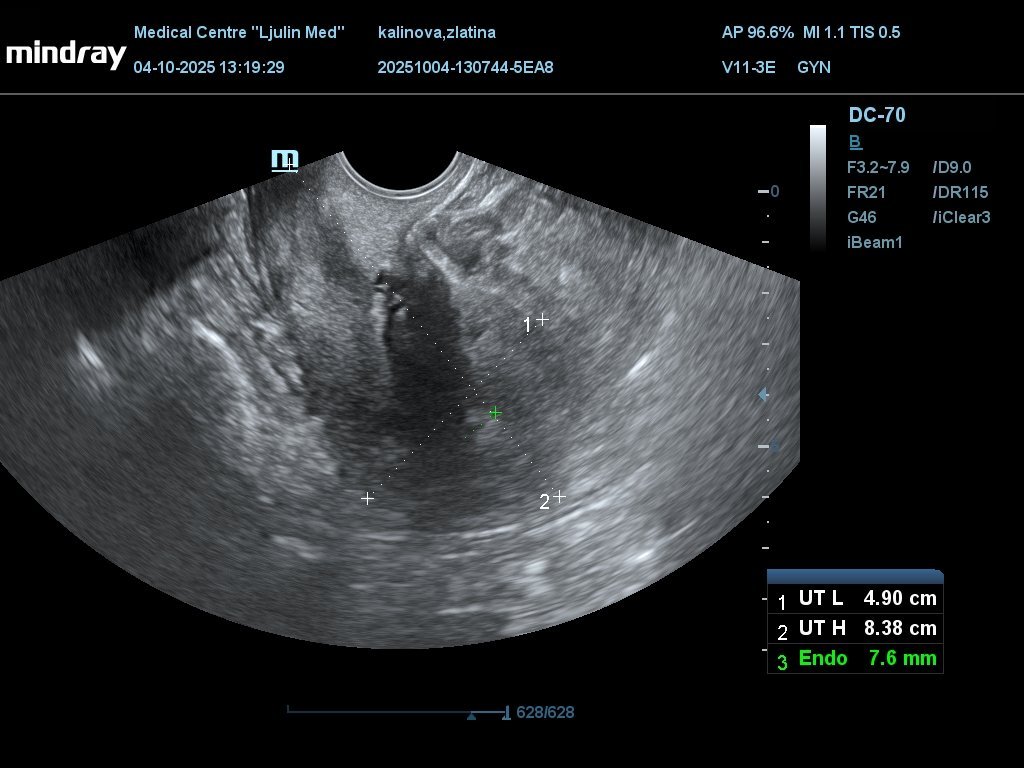

Моля да ми разчетете снимките. Има ли бременност

Последна редакция: сб, 04 окт 2025, 14:11 от Moderator1

Изображенията показват яйчници с антрални фоликули и матка с дебелина на лигавицата 7.6 мм. Във фоликуларна фаза си, демек предстои овулация.

Няма бременност със сигурност.